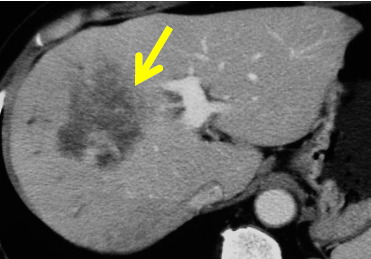

肝内胆管癌の治療法は、外科切除(図4)、化学療法、重粒子線治療などがあります。肝内胆管癌に肝切除を行った場合の5年生存率は約30-50%です。切除が不可能な場合には、胆道癌と同じ化学療法を行います。

図4 摘出された肝内胆管癌(矢印)